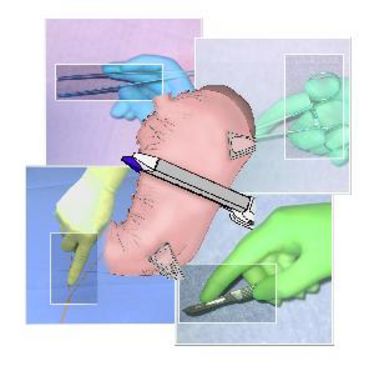

16.03.2011

- 18.03.2011

OP-Kurs "Mikrochirurgie der peripheren Nerven und Gefäße"

OP-Kurs "Mikrochirurgie der peripheren Nerven und Gefäße"